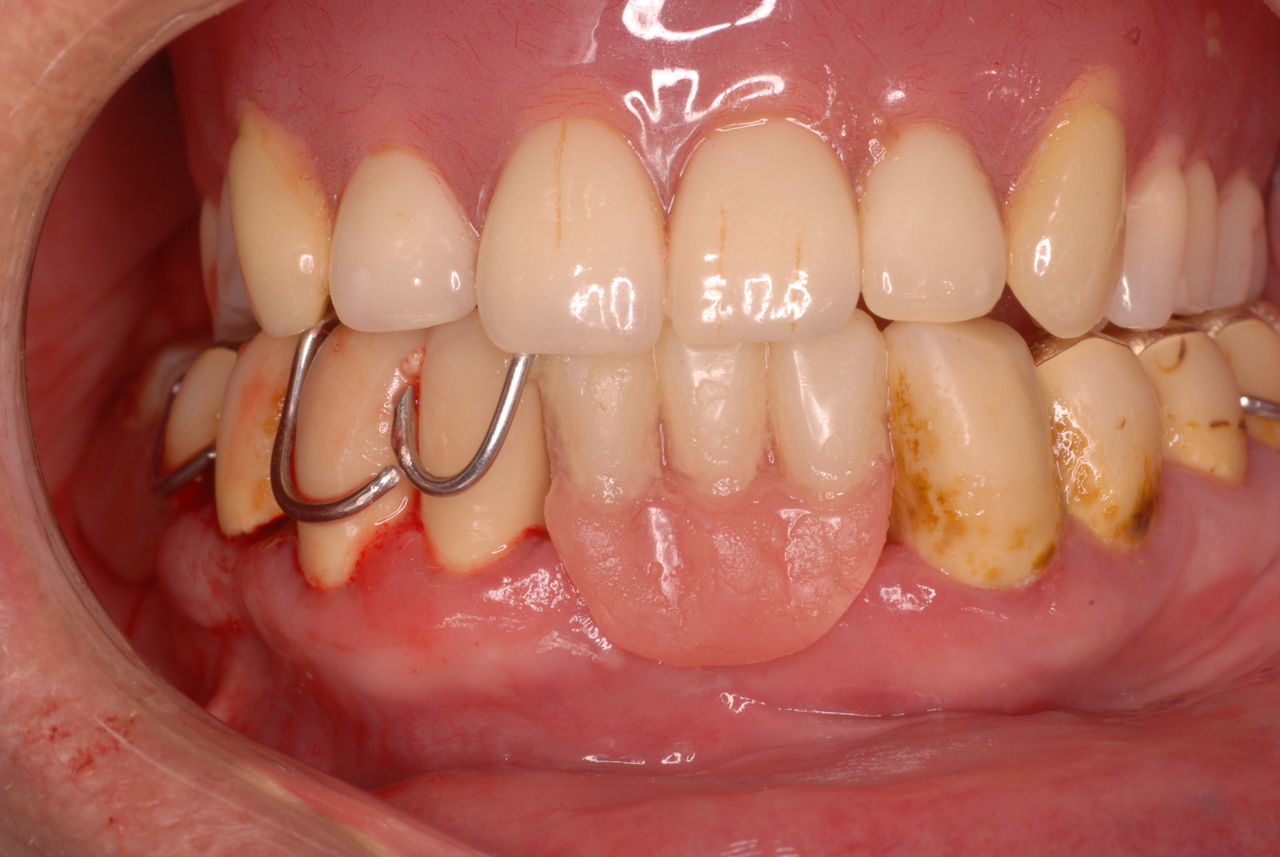

下の歯は数本存在しますが、全て虫歯と歯周病に犯されていました。

食べカスまみれで歯周病に罹患しています。